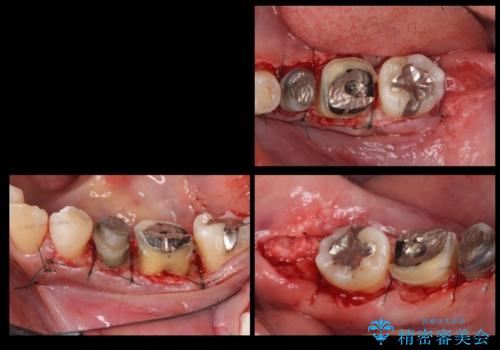

高さがないため、歯肉と歯槽骨の手術(歯周外科手術)APFを行ってから、最終的な被せ物にしました。

高さがない場合は、被せ物が外れやすくなります。高さを出すには向かいの歯を低くするか、まわりの歯茎を下げるか、になります。

今回は歯周外科処置を行い、歯の周りの歯肉の高さをさげるようにしました。

骨からしっかり処置をしないと、歯肉は容易に増殖します。

このような処置は保険適用ではなく自費治療となります。